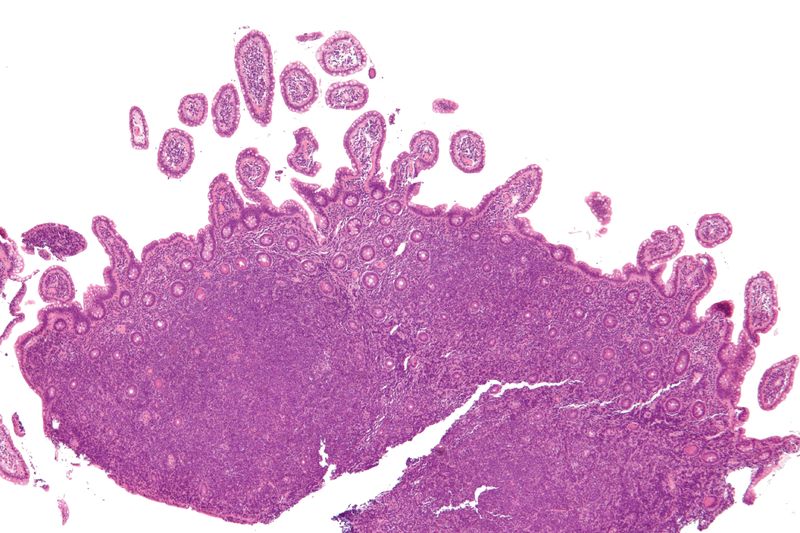

Burkitt lymphoma classically has a high mitotic count and a “starry-sky” histologic appearance due to abundant tingible body macrophages.

Burkitt lymphoma is due to the neoplastic proliferation of intermediate-sized cells (CD20+).